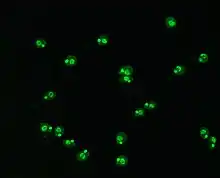

Indirect immunofluorescence

Indirect immunofluorescence is one of the most commonly used tests for ANAs. Typically, HEp-2 cells are used as a substrate to detect the antibodies in human serum. Microscope slides are coated with HEp-2 cells and the serum is incubated with the cells. If the said and targeted antibodies are present then they will bind to the antigens on the cells; in the case of ANAs, the antibodies will bind to the nucleus. These can be visualised by adding a fluorescent tagged (usually FITC or rhodopsin B) anti-human antibody that binds to the antibodies. The molecule will fluoresce when a specific wavelength of light shines on it, which can be seen under the microscope. Depending on the antibody present in the human serum and the localisation of the antigen in the cell, distinct patterns of fluorescence will be seen on the HEp-2 cells.[51][52] Levels of antibodies are analysed by performing dilutions on blood serum. An ANA test is considered positive if fluorescence is seen at a titre of 1:40/1:80. Higher titres are more clinically significant as low positives (≤1:160) are found in up to 20% of healthy individuals, especially the elderly. Only around 5% of the healthy population have ANA titres of 1:160 or higher.[8][53]

There are many nuclear staining patterns seen on HEp-2 cells: homogeneous, speckled, nucleolar, nuclear membranous, centromeric, nuclear dot and pleomorphic. The homogeneous pattern is seen when the condensed chromosomes and interphase chromatin stain. This pattern is associated with anti-dsDNA antibodies, antibodies to nucleosomal components, and anti-histone antibodies. There are two speckled patterns: fine and coarse. The fine speckled pattern has fine nuclear staining with unstained metaphase chromatin, which is associated with anti-Ro and anti-La antibodies. The coarse staining pattern has coarse granular nuclear staining, caused by anti-U1-RNP and anti-Sm antibodies. The nucleolar staining pattern is associated with many antibodies including anti-Scl-70, anti-PM-Scl, anti-fibrillarin and anti-Th/To. Nuclear membrane staining appears as a fluorescent ring around the cell nucleus and are produced by anti-gp210 and anti-p62 antibodies. The centromere pattern shows multiple nuclear dots in interphase and mitotic cells, corresponding to the number of chromosomes in the cell. Nuclear dot patterns show between 13 and 25 nuclear dots in interphase cells and are produced by anti-sp100 antibodies. Pleomorphic pattern is caused by antibodies to the proliferating cell nuclear antigen.[26][53][57][58] Indirect immunofluorescence has been shown to be slightly superior compared to ELISA in detection of ANA from HEp-2 cells.[54]